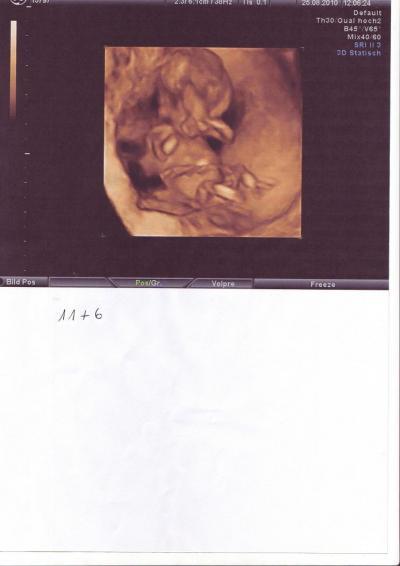

Hallo ihr Lieben, bin wieder da. Das Baby ist super gesund, völlig zeitgerecht entwickelt und sehr lebendig. Die NFM war auch so wie es sein soll. Der Magen und die Blase war gefüllt, keine Hasenschate, Trisomie 21 ist ausgeschlossen, da die Nasenknochen vorhanden sind und die NF zwischen 0.9 und 1,2 cm ist. Bei über 2 cm müssten weitere Untersuchungen gemacht werden. Und: Es wird zu 80 % ein Junge. War gleich zu sehen. Könnte aber auch eine angeschwollene Klitoris sein, was nicht sehr warscheinlich ist. Ein bißchen enttäuscht bin ich schon. Hatte mir nach 2 Jungs so sehr ein Mädchen gewünscht. Aber das ist nunmal so und ich freue mich trotzdem sehr. Nächster Termin ist der 23.09. Mein Geburtstag. Passt doch gut, oder. Und hier die 3D Bilder. GlG

2. Bild